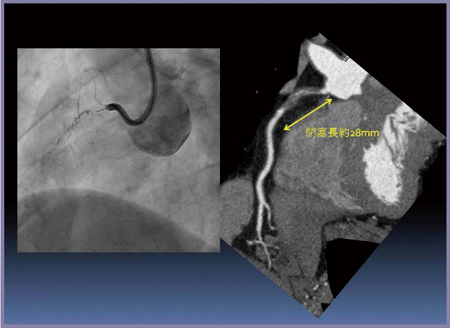

症例4の血管造影では,造影剤が入っていく腔が認められたが,仮に側副血管であった場合,バルーンを膨らませることでperforationを起こし,重篤な合併症が生じる可能性がある。近位部の造影部分をCTで観察すると,血管の外側に沿って降りていくかなり外側を走る腔であり,側副血管である可能性が高いと思われた(図7)。しかし,末梢側は血管の真ん中を通っており,真腔であることが確認できたため,ここにガイドワイヤを通してPCIを行うという治療計画を立てた(図8)。ガイドワイヤの通過後,血管内エコーで管の真腔を通過していることが確認され,冠動脈CTAによる術前評価の有用性が証明された。

図7 症例4:CTAのCPRによる側副血管の確認

血管造影(左)では末梢が描出されず閉塞長も不明。

真腔か側副血管か判別できない。

図8 症例4:CTAによる真腔と側副血管の判定(CTO RCA ♯1)